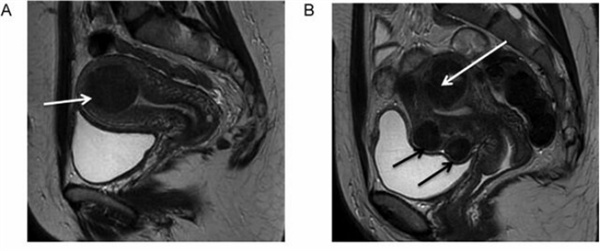

4、磁共振成像:磁共振成像(MRI)可对子宫肌瘤进行精确的定位,有助于了解肿瘤的大小,与宫腔、黏膜、肌层的关系,评估子宫和肿瘤的血管供应。

磁共振成像 T2 加权像子宫肌瘤图像,箭头所示为肌瘤